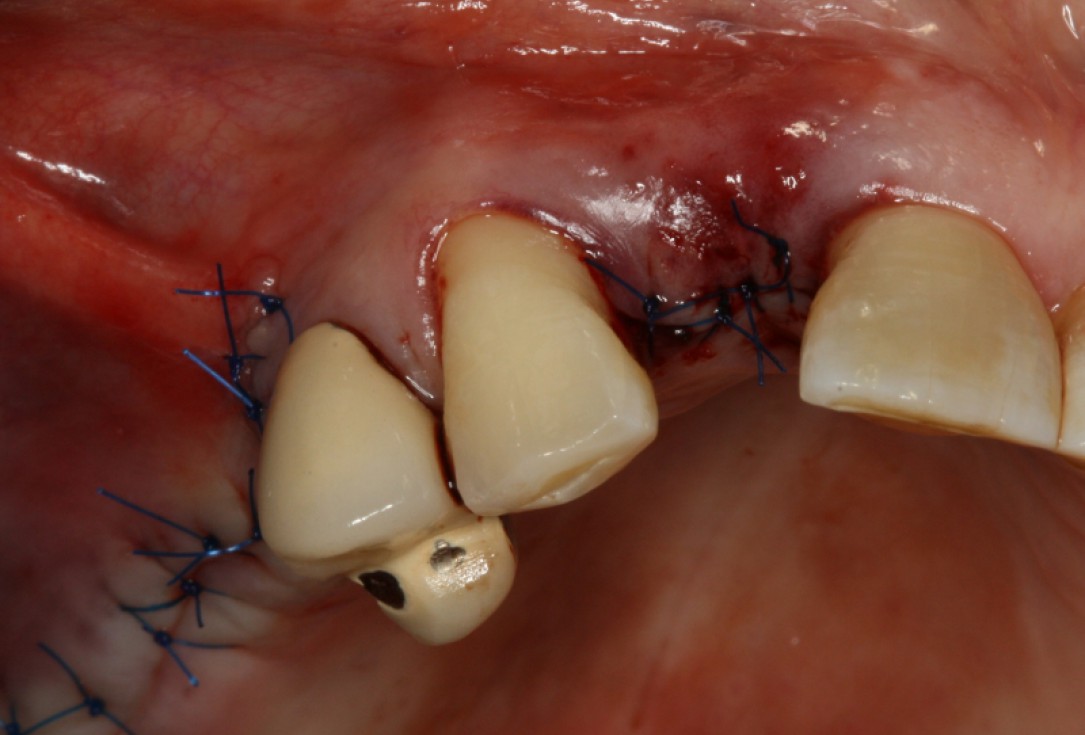

Initial situation: Inflammated tooth #12